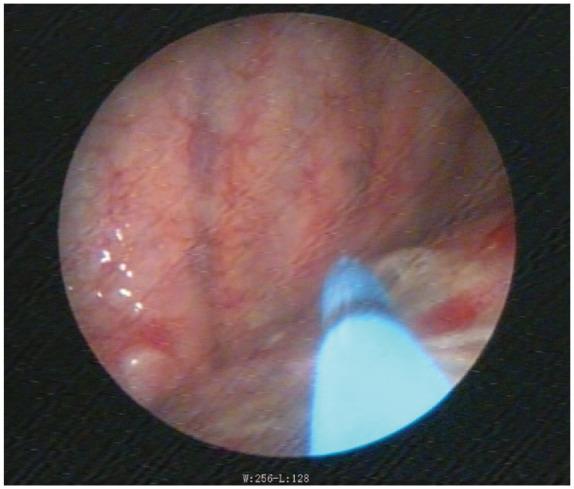

Three male patients with spontaneous pneumothorax were treated; medical thoracoscopy-assisted argon plasma coagulation combined with autologous blood pleurodesis was conducted for all patients whose duration of the air leak exceeded 7 days. We systematically reviewed all of the relevant literature to analyze and sum up the treatments of secondary spontaneous pneumothorax.

The air leaks were all sealed and no recurrence of pneumothorax was reported. No complications of fever, bleeding, or signs of infection were observed during the process.

The authors believe that the combination of medical thoracoscopy-assisted argon plasma coagulation and autologous blood pleurodesis is safe and effective. However, due to the number of patients included in this uncontrolled case study, more cases will be collected in the future.